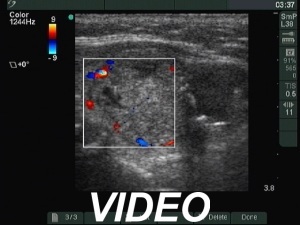

Second examination 7 years later (second and third rows of images):

Ultrasonography. The presentation remained unchanged. Using a better ultrasound device, it turned out that the echogenic granules are related to ventral cystic areas. Therefore, these are not microcalcifications, but figures caused by back wall cystic enhancement.Suggestion: yearly TSH determination, ultrasound in 4 years.

- The interpretation of the discrete lesions in the left lobe is difficult. I mean that this is a dominantly solitary nodule with a peripheral-type cystic portion. (See the explanation at the images.)